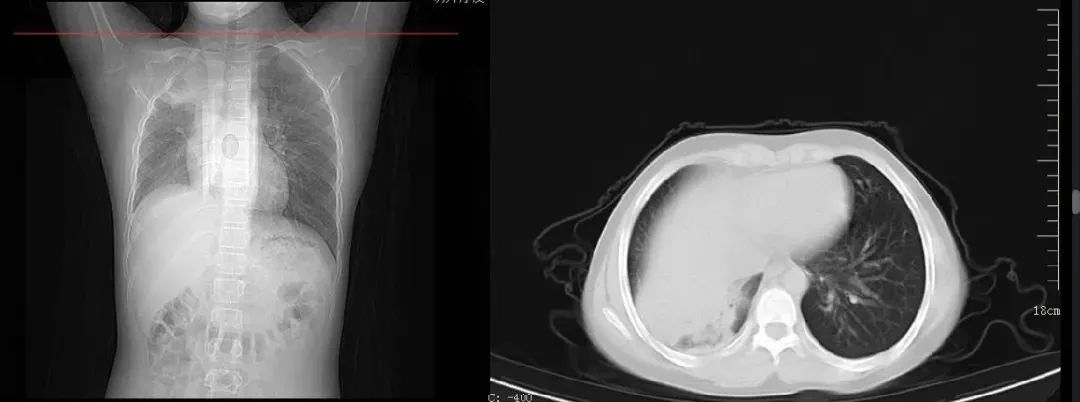

案例二,12歲,男性,確診病例

胸片顯示一側(cè)肺部組織大面積變白

影像所見: 右肺內(nèi)帶見片狀軟組織樣高密度影,右肺野內(nèi)亦可見片狀高密度影,右側(cè)肋膈角變淺變鈍,膈面模糊。考慮右肺部分不張伴胸腔積液可能。